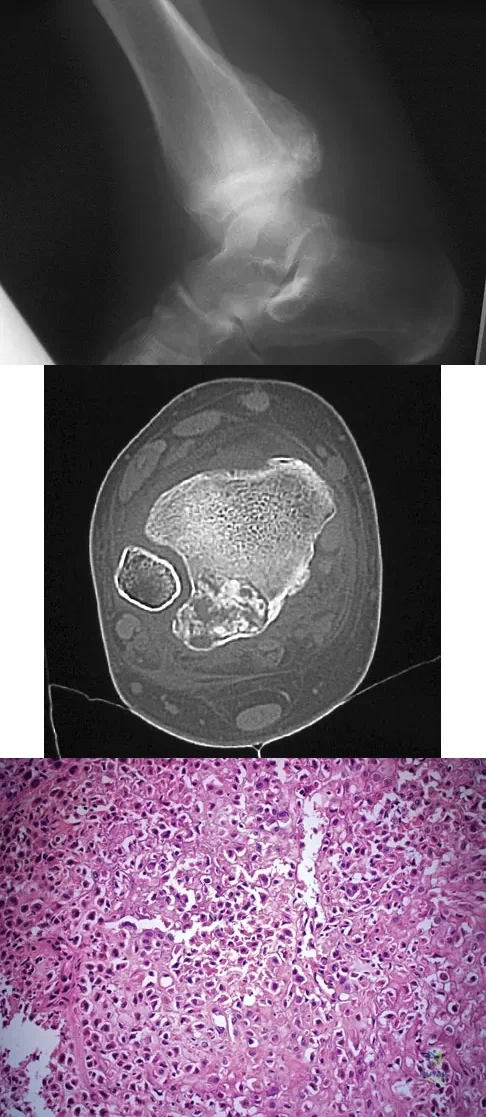

A 13-year-old boy has had pain and swelling in his ankle for the past several months. Based on the radiograph, MRI scan, and biopsy specimen shown in Figures 77a through 77c, what is the best course of action?

Explanation